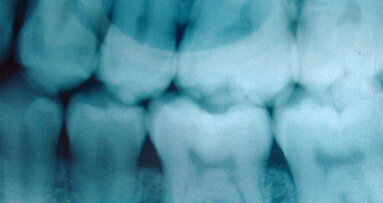

During the 1990s, computer technology gradually replaced hard copy paper records for patients, and scheduling became a more routine process. The influence of computers in the advancement of endodontics was incredible! Many in our profession today don’t remember the “darkroom,” the small, closet-like room in our offices where the developing and fixing of radiograph films was done. One of the most profound changes in dental technology was the advent of digital radiography. Cone-beam computed tomography (CBCT) became a huge asset for a better diagnosis, easier treatment and more predictable results. MTA was introduced as a new root-end filling material and to be used for perforation repairs.